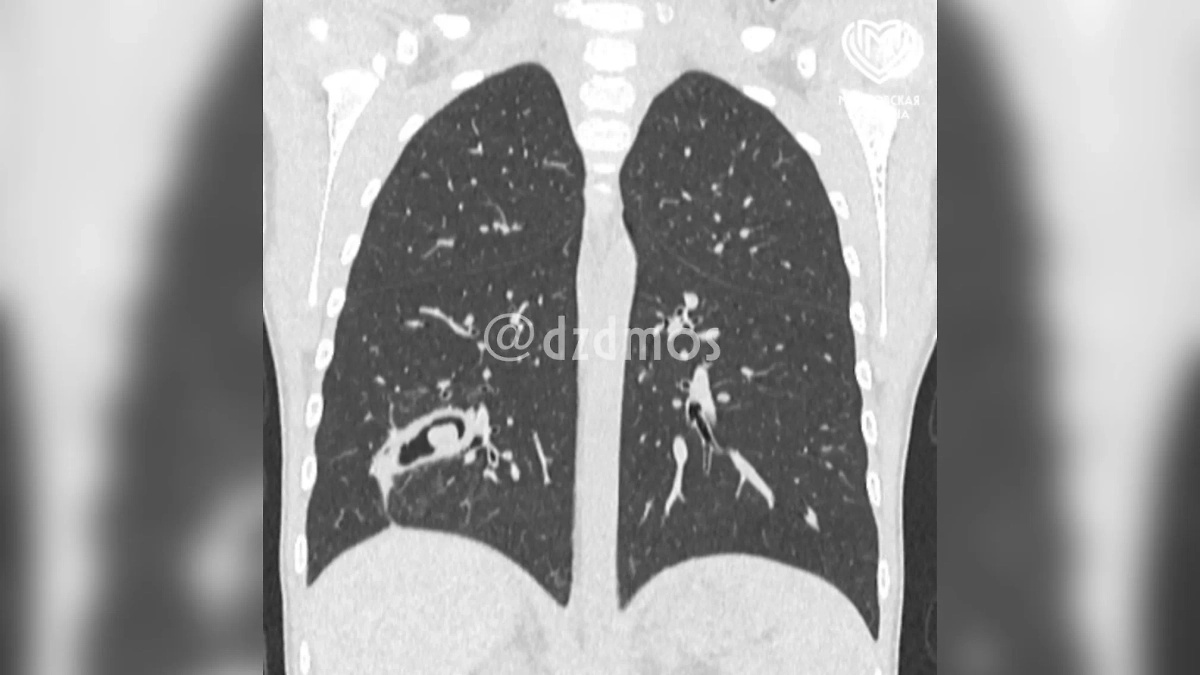

В лёгкое первоклассницы попала шелуха семечки. Фото © Telegram/ Московская медицина

Компьютерная томография показала, что скорлупа семечки буквально врослась в третий субсегмент правого лёгкого, спровоцировав бронхоэктаз — тяжёлое поражение бронхов с накоплением гнойного содержимого. Врачи провели прецизионную операцию: сначала очистили бронхи от гноя, затем с помощью эндоскопической техники аккуратно извлекли инородный объект.